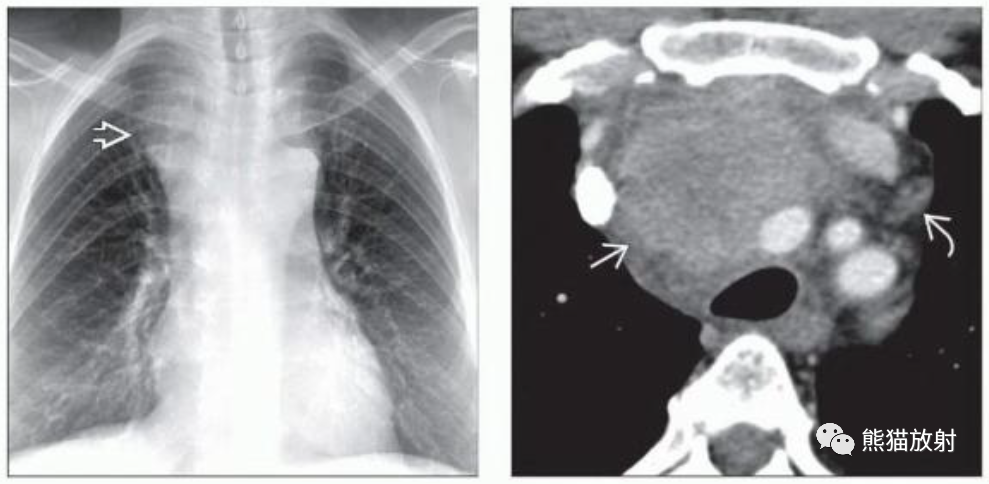

(左) 胸腺瘤患者的胸片显示纵隔偏右侧肿块(箭),边界清楚,轻度分叶。在正位胸片上胸腺瘤常表现为纵隔轮廓异常。

(左) 胸腺癌。胸片显示软组织肿块导致上纵隔增宽。

(右) 轴位CT显示一个不规则不均质强化的前纵隔肿块,周围见软组织条索影并增大淋巴结。虽然胸腺恶性肿瘤在影像学上很难与胸腺瘤相鉴别,但淋巴结病和远处转移提示胸腺癌或胸腺类癌。

(左) 胸腺癌。CT显示一个巨大不均质强化的左前纵隔肿块,侵犯左前胸壁,对纵隔血管产生占位效应。胸膜转移可见于胸腺恶性肿瘤,但它是侵袭性胸腺瘤的特征。